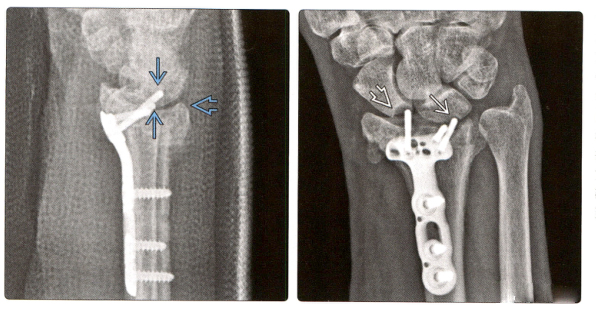

6. (Снимок слева) КТ поперечного сечения показывает винты, которые фиксируют ладонной пластинку. Латеральный винт воздействует непосредственно на сухожилие лучевого разгибателя запястья.

(Изображение справа) Сагиттальная КТ показывает перелом дистального отдела лучевой кости, который был успешно залечен путем открытой репозиции и внутренней фиксации. Больной испытывает боль при разгибании запястья. Проксимальный бикортикальный винт воздействует непосредственно на мышцы-разгибатели.

7. (Фото слева) КТ с корональной реконструкцией показывает оссификацию межкостной перепонки после ORIF и перекрестного спондилодеза при лечении оскольчатых внутрисуставных переломов дистального отдела лучевой кости и переломов диафиза локтевой кости. Виден кончик винта.

(Справа) МРТ с корональным градиентным эхо показывает разрыв TFCC и ладьевидно-полулунной связки у этого пациента.